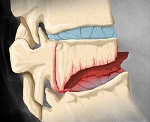

Позвоночник состоит из отдельных костей – позвонков, соединенных между собой связками, хрящами и мелкими суставами. Каждый позвонок образован обращенным вперед телом и обращенной назад дугой. В пространстве между задней поверхностью тела и передней поверхностью дуги находится спинной мозг. В норме тело позвонка имеет цилиндрическую форму, высота его переднего и заднего отделов примерно одинакова. При компрессионном переломе передние отделы позвонка сдавливаются, и он принимает клиновидную форму. Повреждение может возникать в любом отделе позвоночника, однако чаще всего страдает переходный отдел (нижние грудные и верхние поясничные позвонки).

• Компрессионный перелом. Сопровождается сдавлением, раздроблением и клиновидным сплющиванием переднего отдела позвонка. Выделяют три степени компрессии: 1 степень – уменьшение высоты тела на 1/3 или менее, 2 степень – уменьшение высоты тела на 1/3-1/2, 3 степень – уменьшение высоты тела на 1/2 или более. Чаще страдает один позвонок, реже наблюдается повреждение нескольких соседних позвонков. Дужки, суставные отростки и межпозвонковые диски при таких переломах не страдают. Подобные повреждения часто возникают при падениях с высоты, при падении на ноги возможно сочетание с переломом пяточных костей, при падении на ягодицы – с переломом таза.

• Раздробленный (оскольчатый) перелом. Сопровождается вклиниванием переднего края вышележащего позвонка в тело нижележащего. Межпозвонковый диск разрушается, краевой отломок позвонка выдвигается кпереди. Иногда фрагмент тела смещается кзади, вызывая повреждение спинного мозга.

• Переломовывих. Сопровождается смещением верхних отделов позвоночника кпереди. Сочетается со сдвигом межсуставных поверхностей или с повреждением суставных отростков и дужек. Осложняется ушибом, сдавлением или разрывом нервных корешков и спинного мозга.